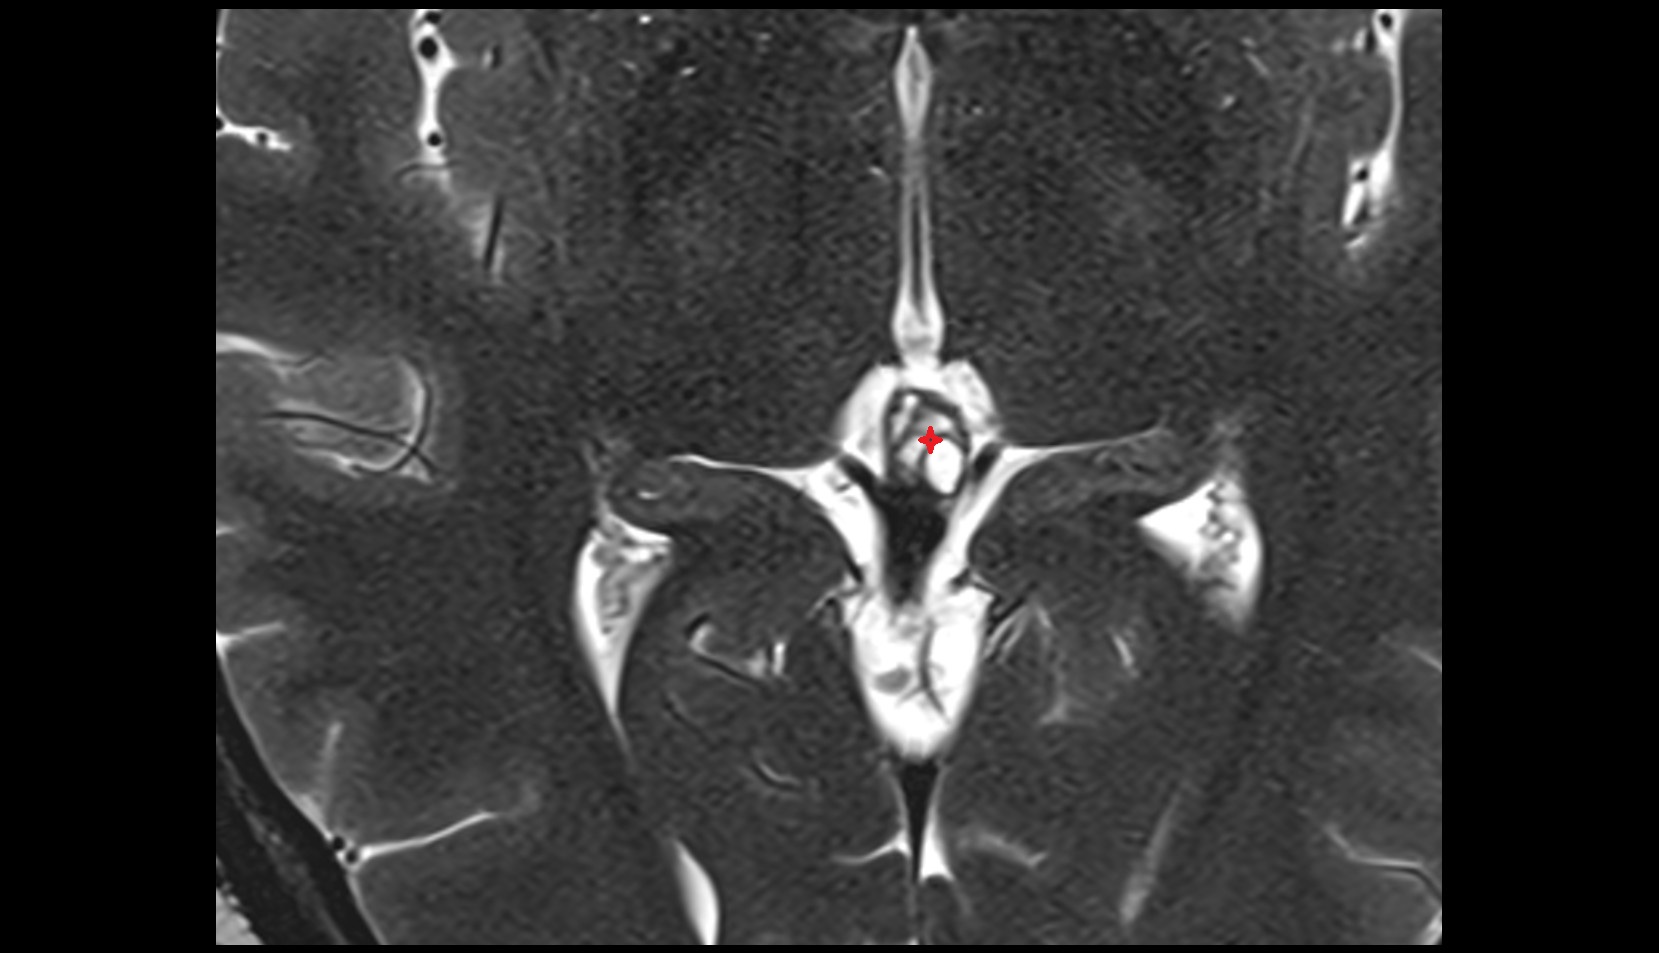

- Median aperture of fourth ventricle (foramen of Magendie)

- Lateral aperture of fourth ventricle (foramen of Luschka)